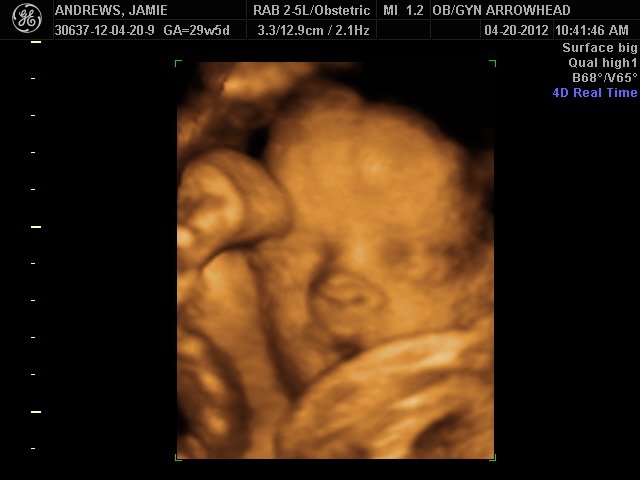

We offer complimentary 3D/4D Ultrasounds to all our OB patients around 30 weeks! The following photos are some examples of our work, shown with permission from our patients.